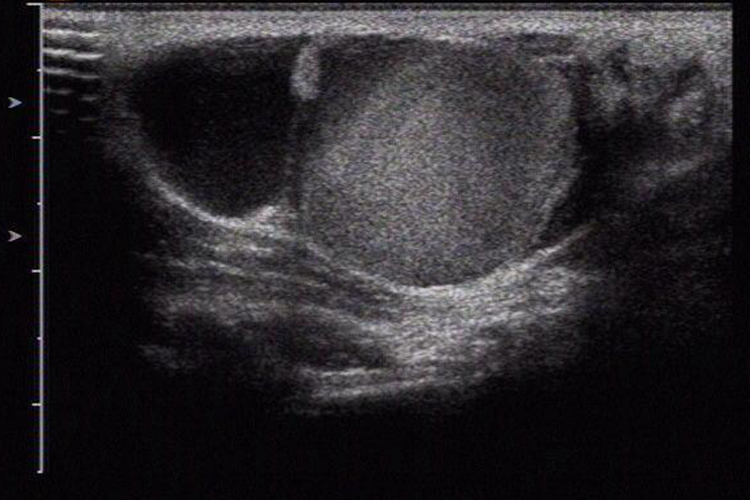

蔓状血管瘤

超声多表现为管状、瘤样或梭形无回声或低回声,相互交通,呈大小不等的网格状或蜂窝样分布。大者形态不规则,边界不清, 部分可见云雾样低回声。较小者多为无回声,边界尚清。彩色多普勒血流图像不需加压即可见管腔内充满红蓝色血流。